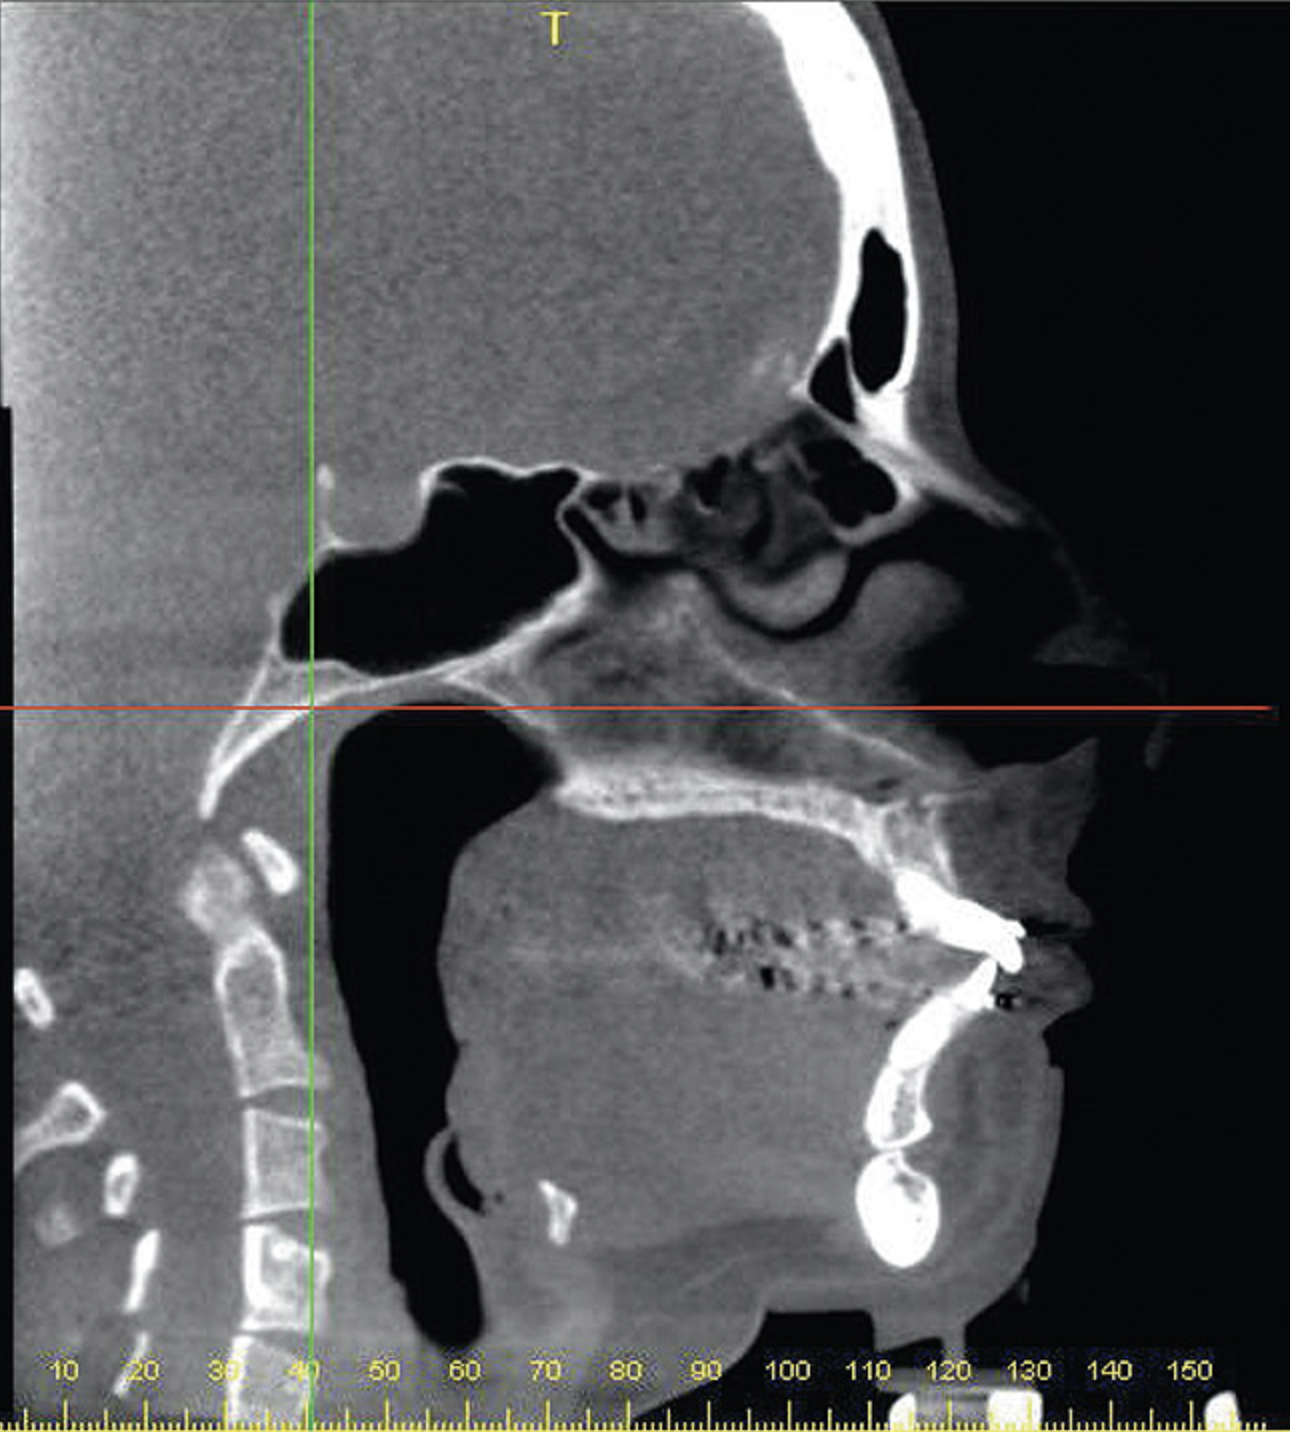

A stable TMJ is critical in establishing a normal functional occlusion. Unless the condyles are in a stable musculoskeletal position, there are always interferences to normal function and stress placed on the masticatory system.1-3,15 In orthodontics, the Angle classification of malocclusion using handheld models has been the standard to evaluate the fit of the teeth. However, it is not possible to truly identify the occlusion/malocclusion using handheld models. Before the occlusion can be evaluated, the clinician must ascertain the joint position and condition (Figure 7 and Figure 8).1,16

Figure 7A  This case is an example of the importance of evaluating the bite with the joints seated in a stable position. Orthodontic treatment was rendered to correct a

Figure 7A

Figure 7B  This case is an example of the importance of evaluating the bite with the joints seated in a stable position. Orthodontic treatment was rendered to correct a

Figure 7B

Figure 7C This case is an example of the importance of evaluating the bite with the joints seated in a stable position. Orthodontic treatment was rendered to correct a

Figure 7C

Figure 7D  This case is an example of the importance of evaluating the bite with the joints seated in a stable position. Orthodontic treatment was rendered to correct a

Figure 7D